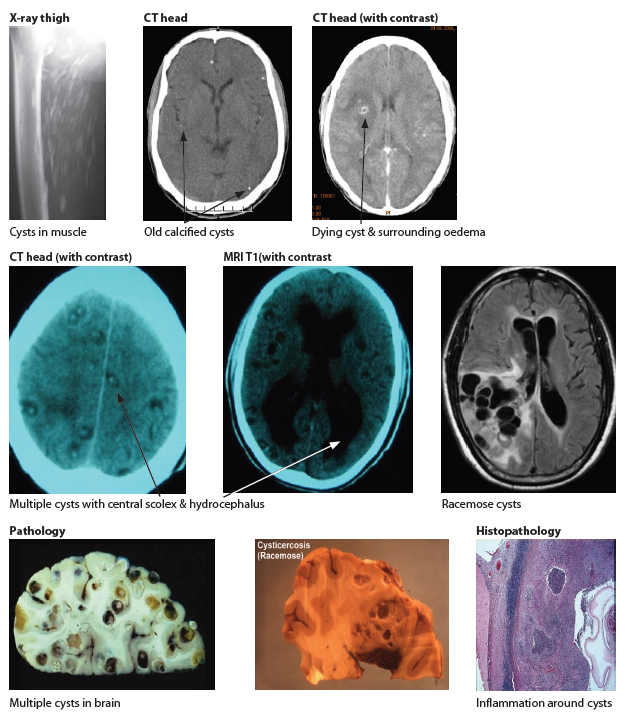

• Neurocysticercosis (Taenia solium a pork parasite)